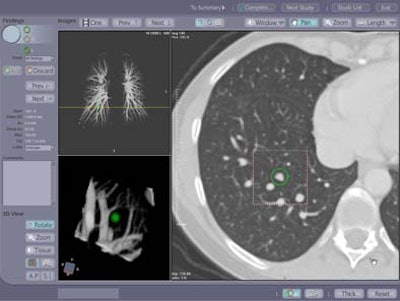

| Contrast enhanced spiral CT study in a 49-year-old woman with a history of colon cancer. A 7-mm soft tissue lung lesion was missed at clinical interpretation but detected by CAD. The location of the lesion in the immediate vicinity of lung vessels of similar size may have prevented its detection at the initial readout. A yellow line indicates the anatomical level of the displayed section within the volume data set in a coronal maximum intensity projection of the pulmonary vascular tree (left upper image panel). 3D volume rendering (left lower image panel) of the lesion highlighted in green displays the spatial relationship of the lesion relative to surrounding vascular structures and enables better differentiation of focal lung lesions and vessels than individual axial sections. Image courtesy of Dr. Joseph Schoepf. |